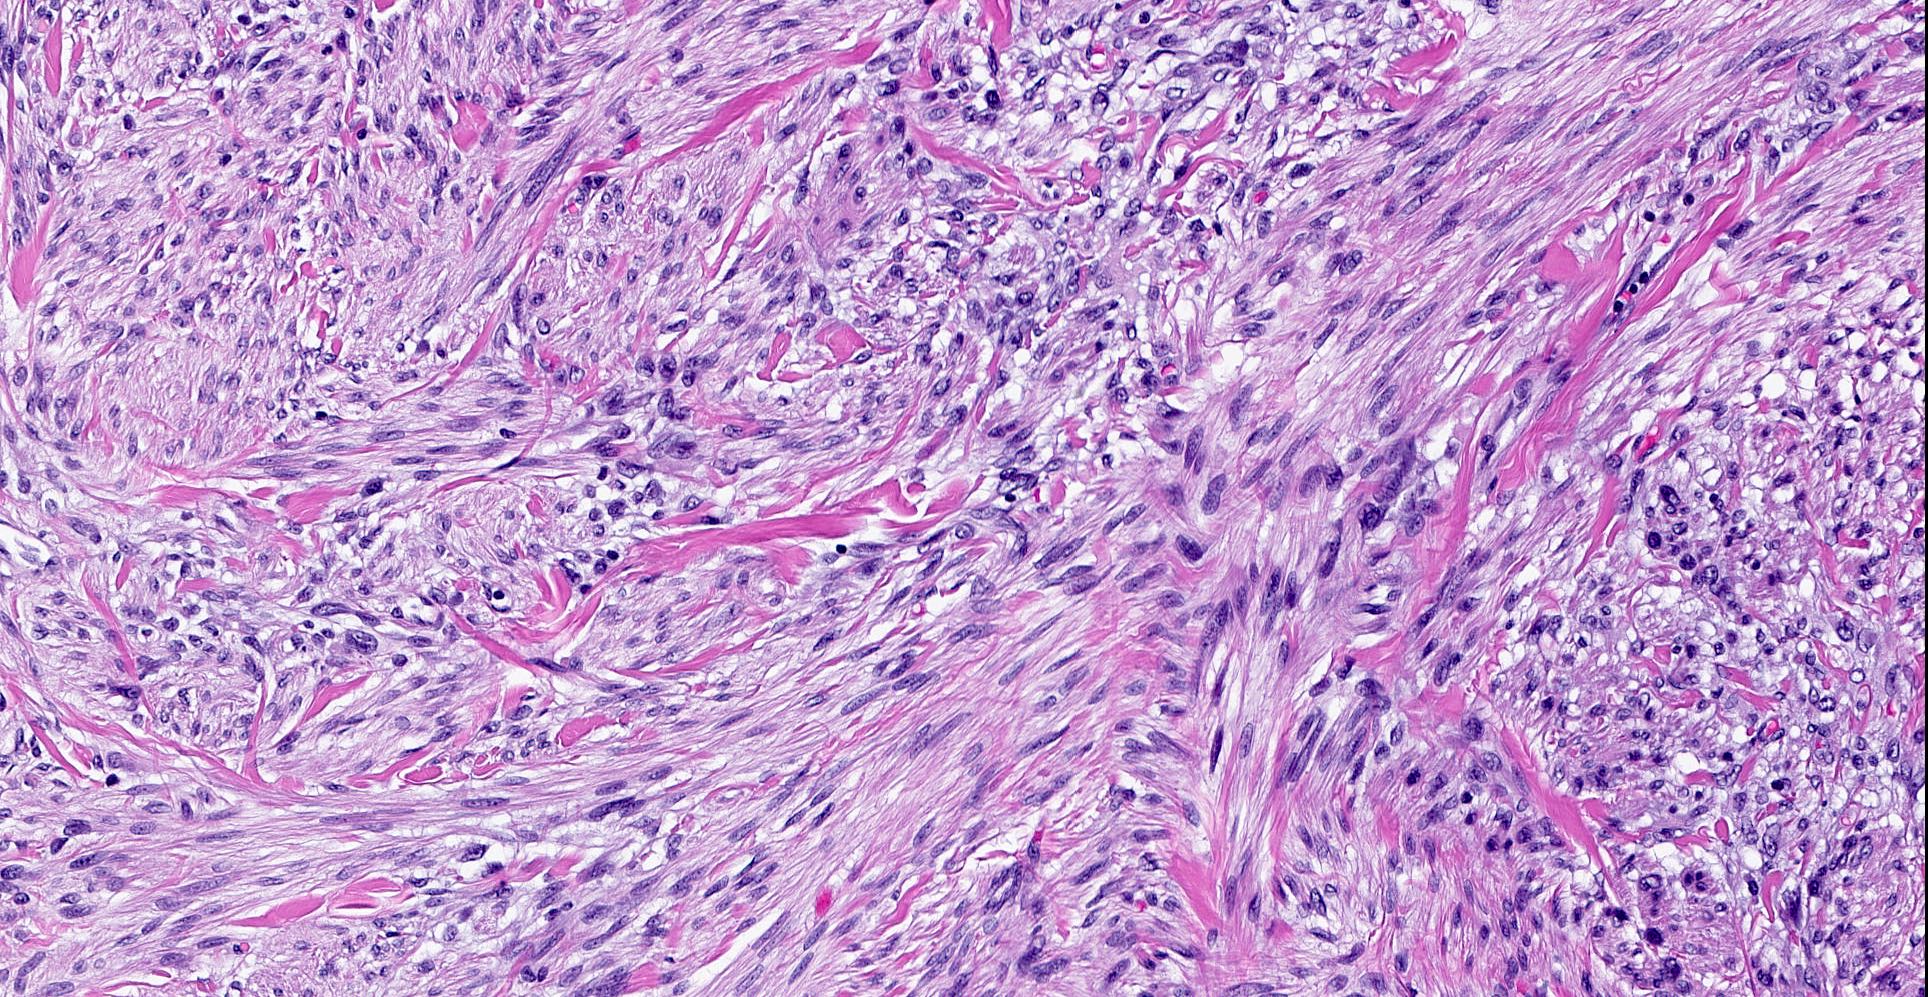

Microscopic (histologic) description

- Well circumscribed, lacks true capsule, rarely infiltrative

- Bland, uniform, short to elongated spindle cells arranged as short haphazard intersecting fascicles admixed with bands of hyalinized, brightly eosinophilic collagen and variable amounts of fat

- No more than mild nuclear atypia

- Mitoses usually absent, atypical mitoses and necrosis absent

- Mast cells common, perivascular lymphocytic infiltrates on occasion

- Focal myxoid stromal changes common

- May show smooth muscle leiomyomatous differentiation (elongated spindle cells with cigar shaped nuclei and pink cytoplasm)

- Rarely cartilaginous or osseous components

- Variants:

- Collagenized / fibrous: collagenous stroma predominates, may have hypocellular myofibroblastic spindle cell component

- Cellular: dense proliferation of myofibroblasts, ratio of spindle cells to collagen increased compared with classical variant, may have infiltrative borders, storiform or herringbone arrangement

- Infiltrative: irregular margins, grows into surrounding mammary parenchyma entrapping glandular tissue

- Myxoid: stellate and spindle cells in abundant myxoid stroma (Histol Histopathol 2016;31:1)

- Deciduoid: large round, polygonal cells with abundant eosinophilic glassy cytoplasm, single or multiple prominent nucleoli which may be eccentrically placed, binucleation, sharp cell borders, eosinophilic intracytoplasmic inclusions (Histopathology 2008;52:652)

- Lipomatous: abundant adipocytic component

- Epithelioid: oval to polygonal cells arranged in clusters, cords, alveolar groups, linear strands, mono, bi or multinucleated, may have eccentrically placed nuclei with small nucleoli, well defined cell borders, single file arrangement may mimic invasive lobular carcinoma (Am J Surg Pathol 2009;33:1085)

- Atypical: single or scattered atypical mono or multinucleated cells with mild to severe nuclear pleomorphism, regarded as degenerative (Arch Pathol Lab Med 2008;132:1813)

Microscopic (histologic) images